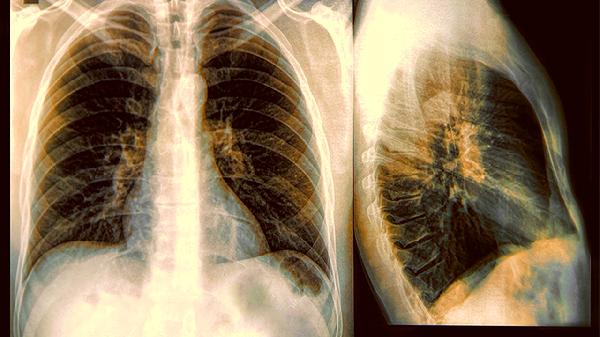

睡觉时频繁出现3种情况,或暗示肺部病变,肺癌患者也有类似表现